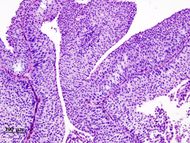

Histopathology of urothelial carcinoma of the urinary bladder. Transurethral biopsy. H&E stain. | |

90% من حالات سرطان المثانة هي Transitional cell carcinomas (TCC) التي تنشأ من البطانة الداخلية للمثانة المسماة urothelium. العشرة بالمائة الباقية من الأورام هي squamous cell carcinoma, adenocarcinoma, sarcoma, small cell carcinoma وتراكمات ثانوية من سرطانات أماكن أخرى بالجسم.